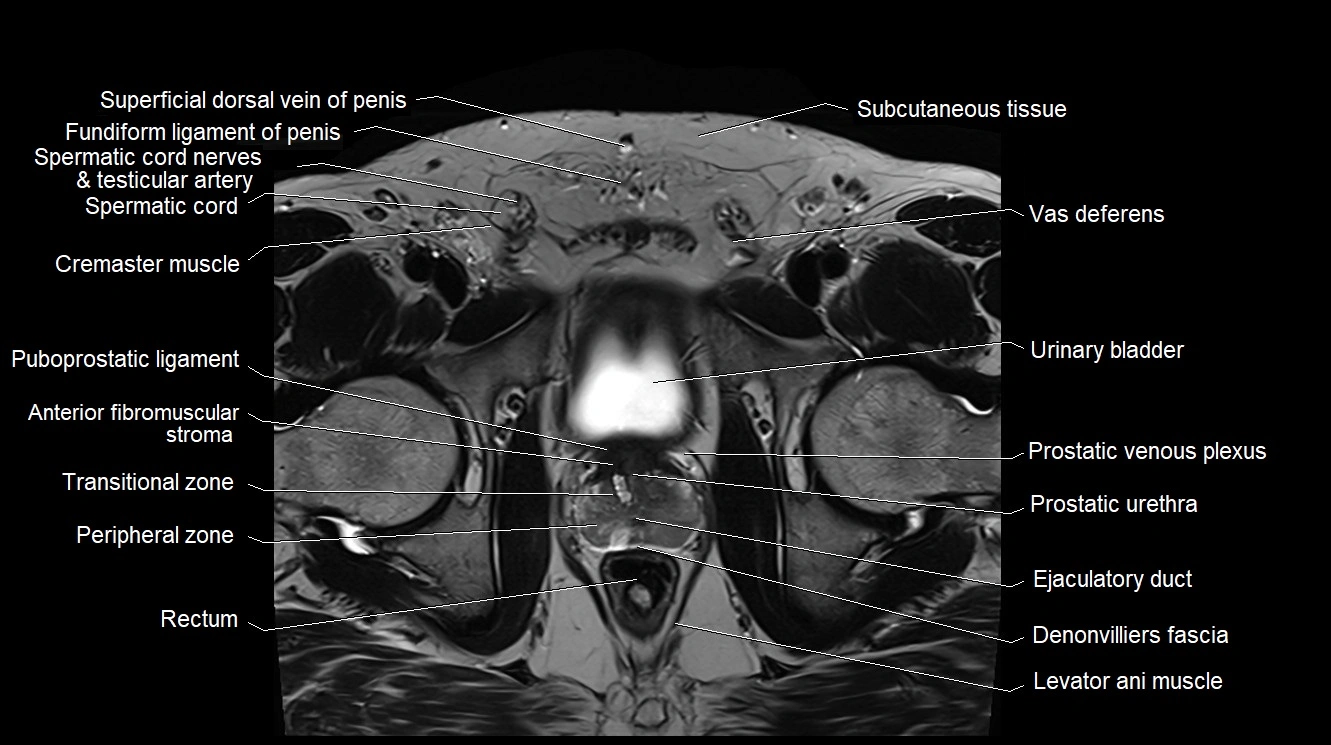

MRI image